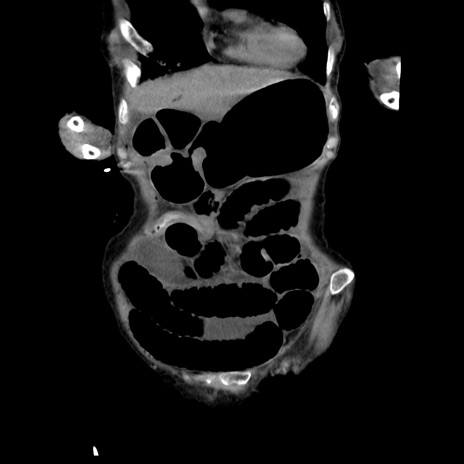

横断像